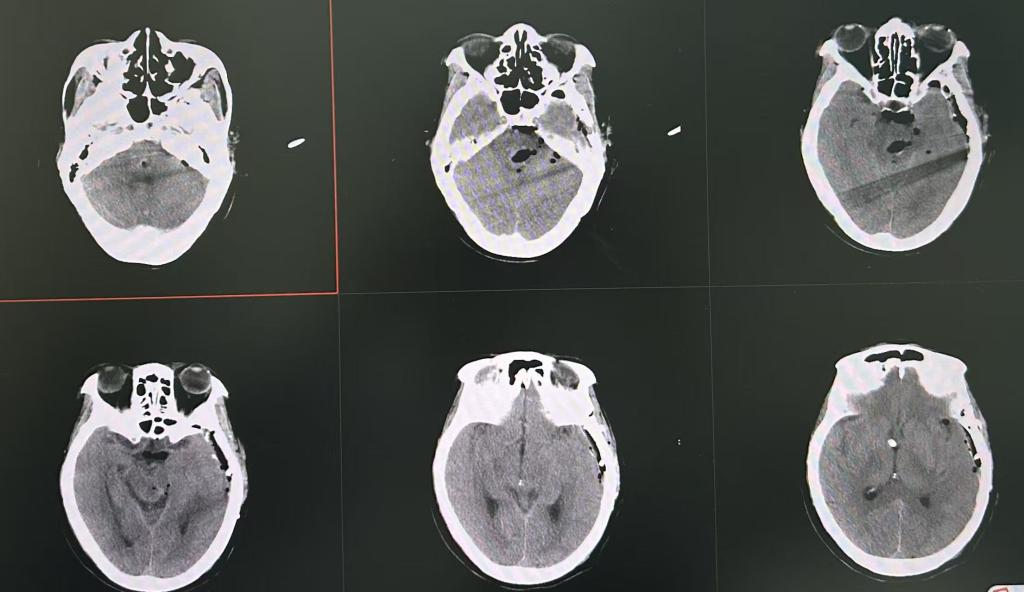

患者术前CT

“患者送来时已深度昏迷,CT显示脑干血肿达6.7毫升,病情凶险。”神经外科副主任池超超回忆起接诊场景仍记忆犹新。脑干出血发病急、进展快,且病灶周围布满神经核团与血管,手术稍有偏差便可能导致不可逆的神经损伤,甚至直接危及生命。面对这场硬仗,神经外科沉着应战,制定手术方案,由池超超副主任医师主刀,周元鼓副主任医师助手,在神经导航下显微镜联合神经内镜辅助开颅脑干血肿清除术。